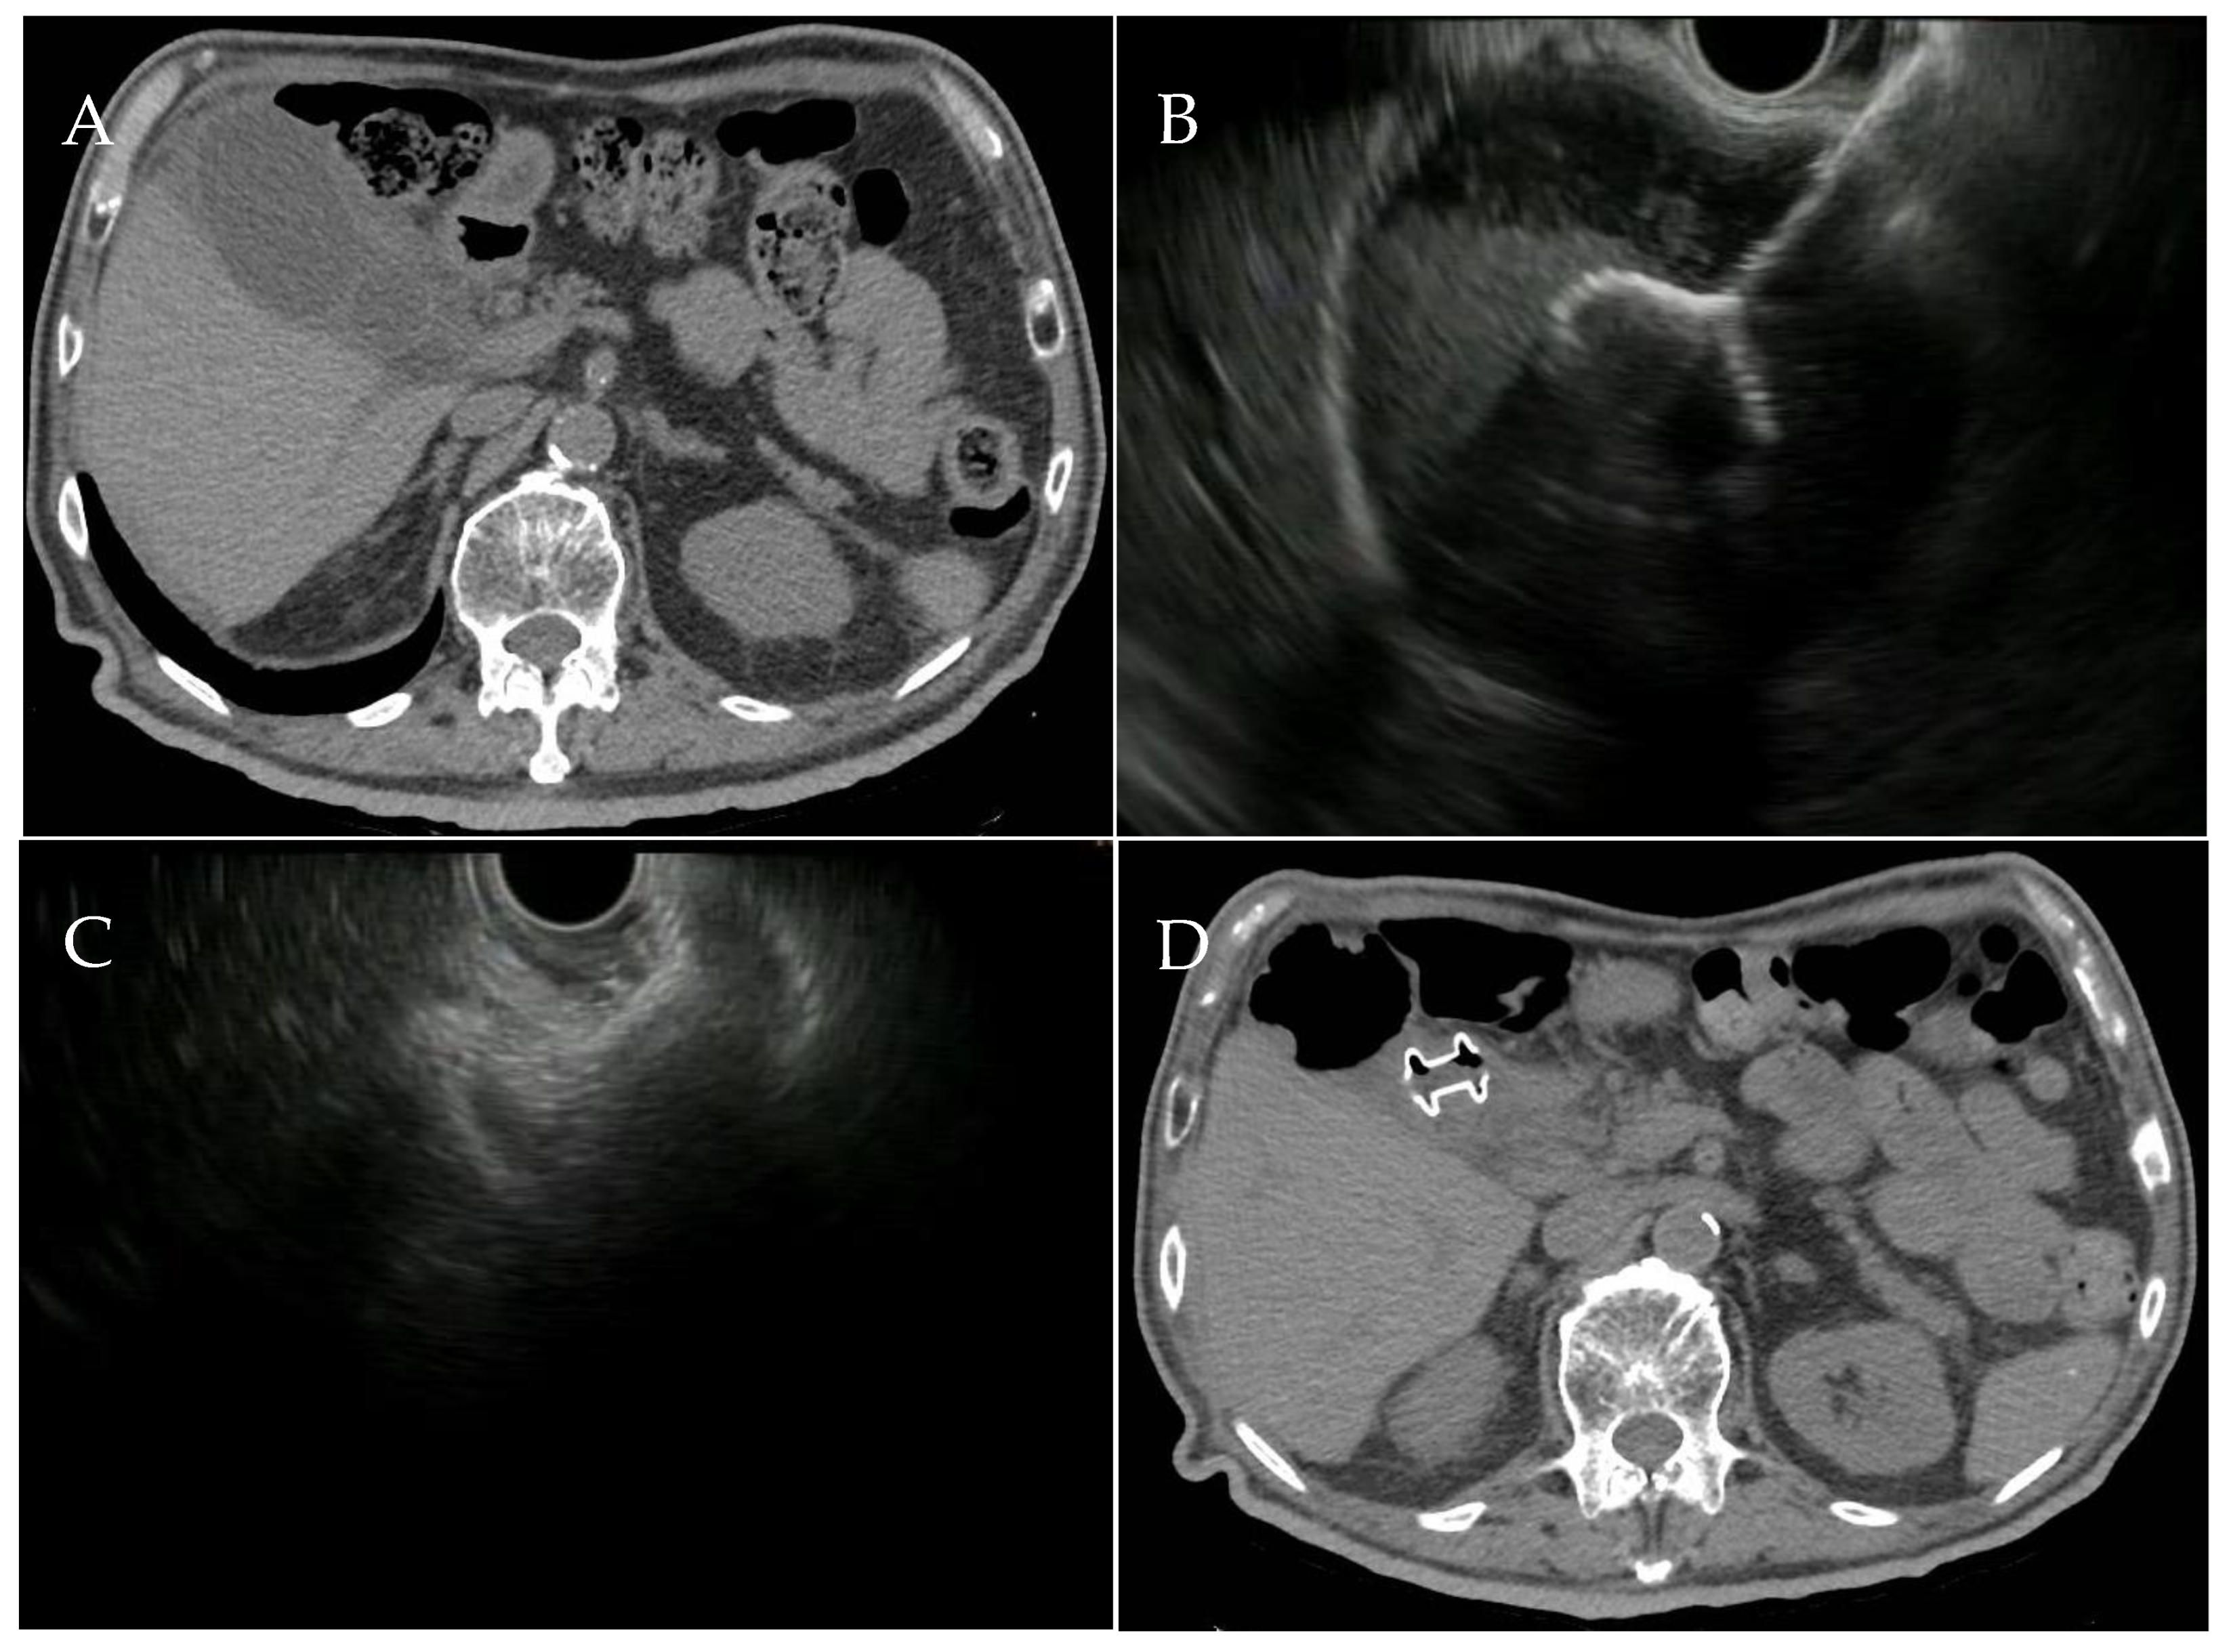

2. Transpapillary Endoscopic Gallbladder Drainage: Technical Aspects

3. EUS-Guided Gallbladder Drainage: Technical Aspects